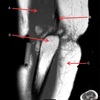

INFRASPINATUS MUSCLE

How well did you know this?

1

Not at all

2

3

4

5

Perfectly

10

Q

What is letter D?

A

GLENOID